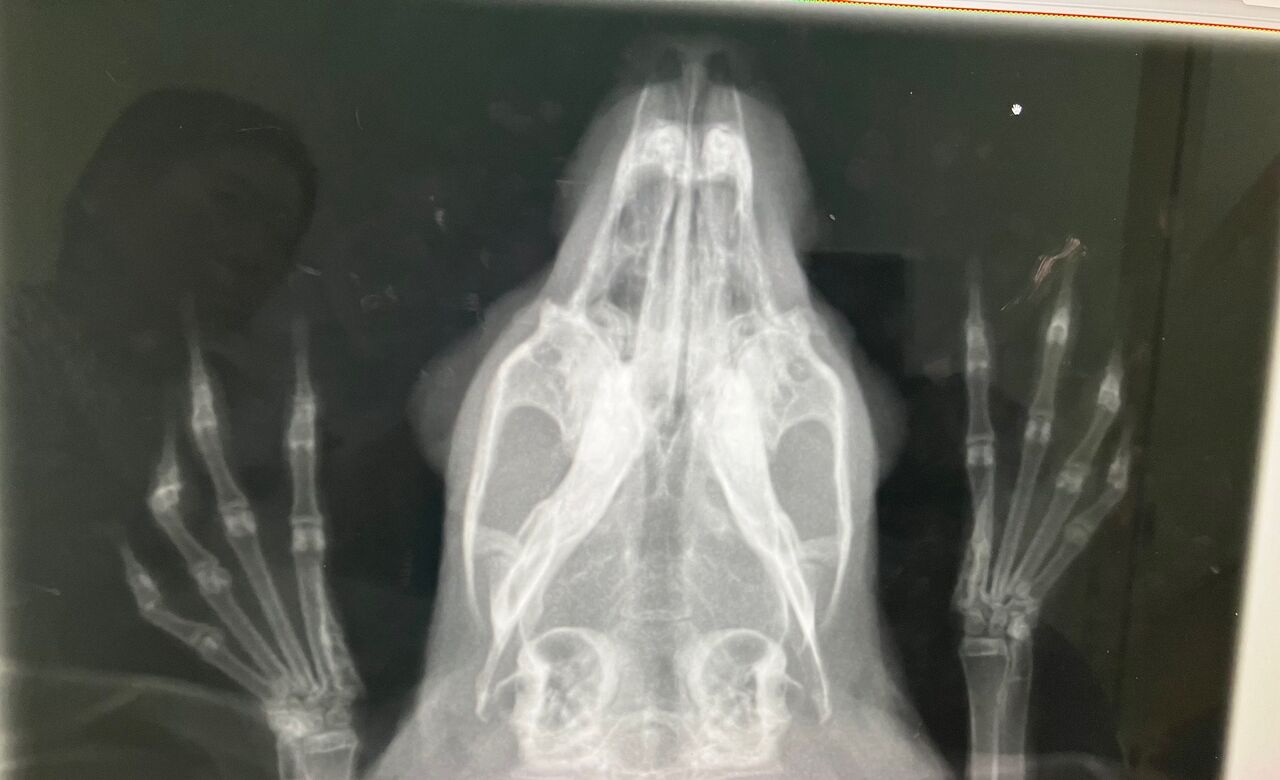

そして11月27日、避妊手術

術前の血液検査、レントゲン、特に問題ありませんでしたが、

口内検査で歯、奥歯右下3番目が少し内側に向いてたのでカット処置。